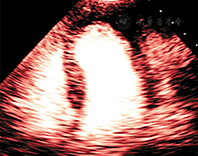

是由于大量的造影剂充满在图像的近场及感兴趣区域。主要成因是单位时间内注射了过量的造影剂(注射速度太快或造影剂浓度太高)。随着时间的推移,造影剂在心室腔的浓度将渐渐减少,等待衰减伪像平息后即可继续获取图像。衰减还可能出现在左室胸骨旁长轴观切面,右室处造影剂气泡的破坏形成阴影笼罩在左室上方,影响了对左室的观察。心尖长轴切面的三腔心切面可以作为更好的观察切面。